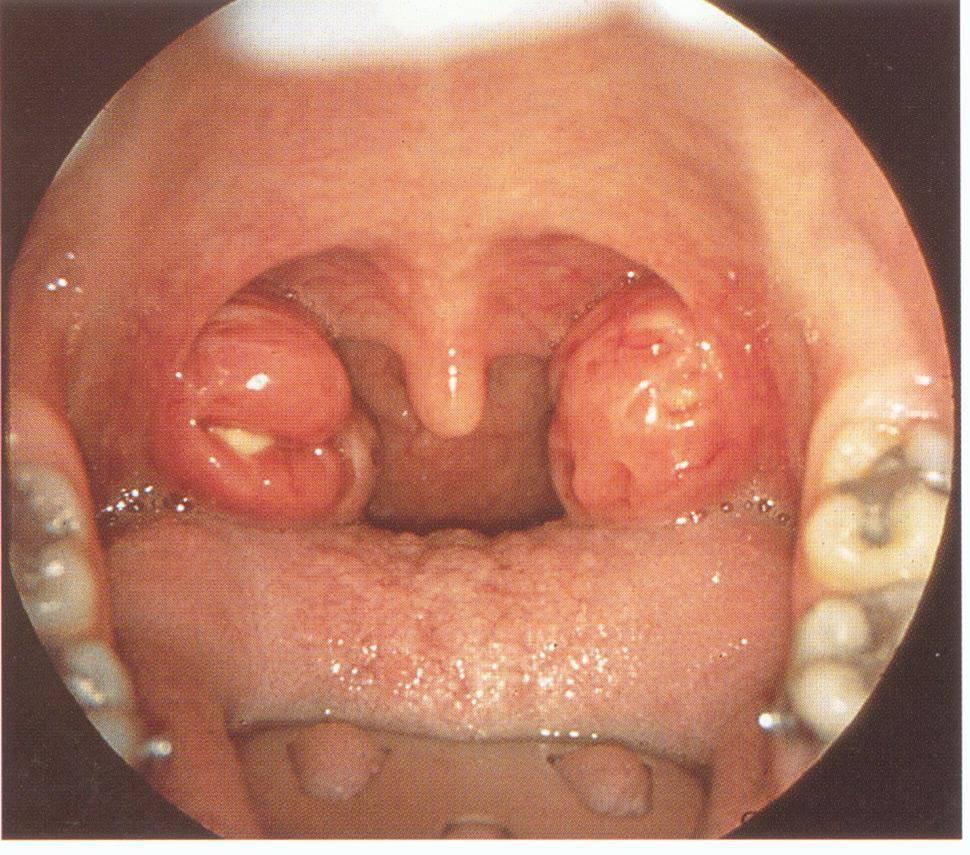

(1)患者呈急性病容,表情痛苦,因剧烈咽痛和张口困难,检查常不合作。(2)早期周围炎时,可见一侧舌腭弓显著充血。若局部明显隆起,甚至张口困难,提示脓肿已形成。(3)前上型者,患侧腭舌弓及软腭红肿突出,悬雍垂水肿,偏向对侧,舌腭弓上方隆起,扁桃体被遮盖且推向内下方。病程7~10天者,有的脓肿可自行破溃排脓。

(4)属后上型者,患侧咽腭弓红肿呈圆柱状,扁桃体被推向前下方,软腭与悬雍垂可无水肿,常无张口困难。但是,炎症可向下扩散至喉咽部及喉入口等处,可引起喉水肿等并发症。